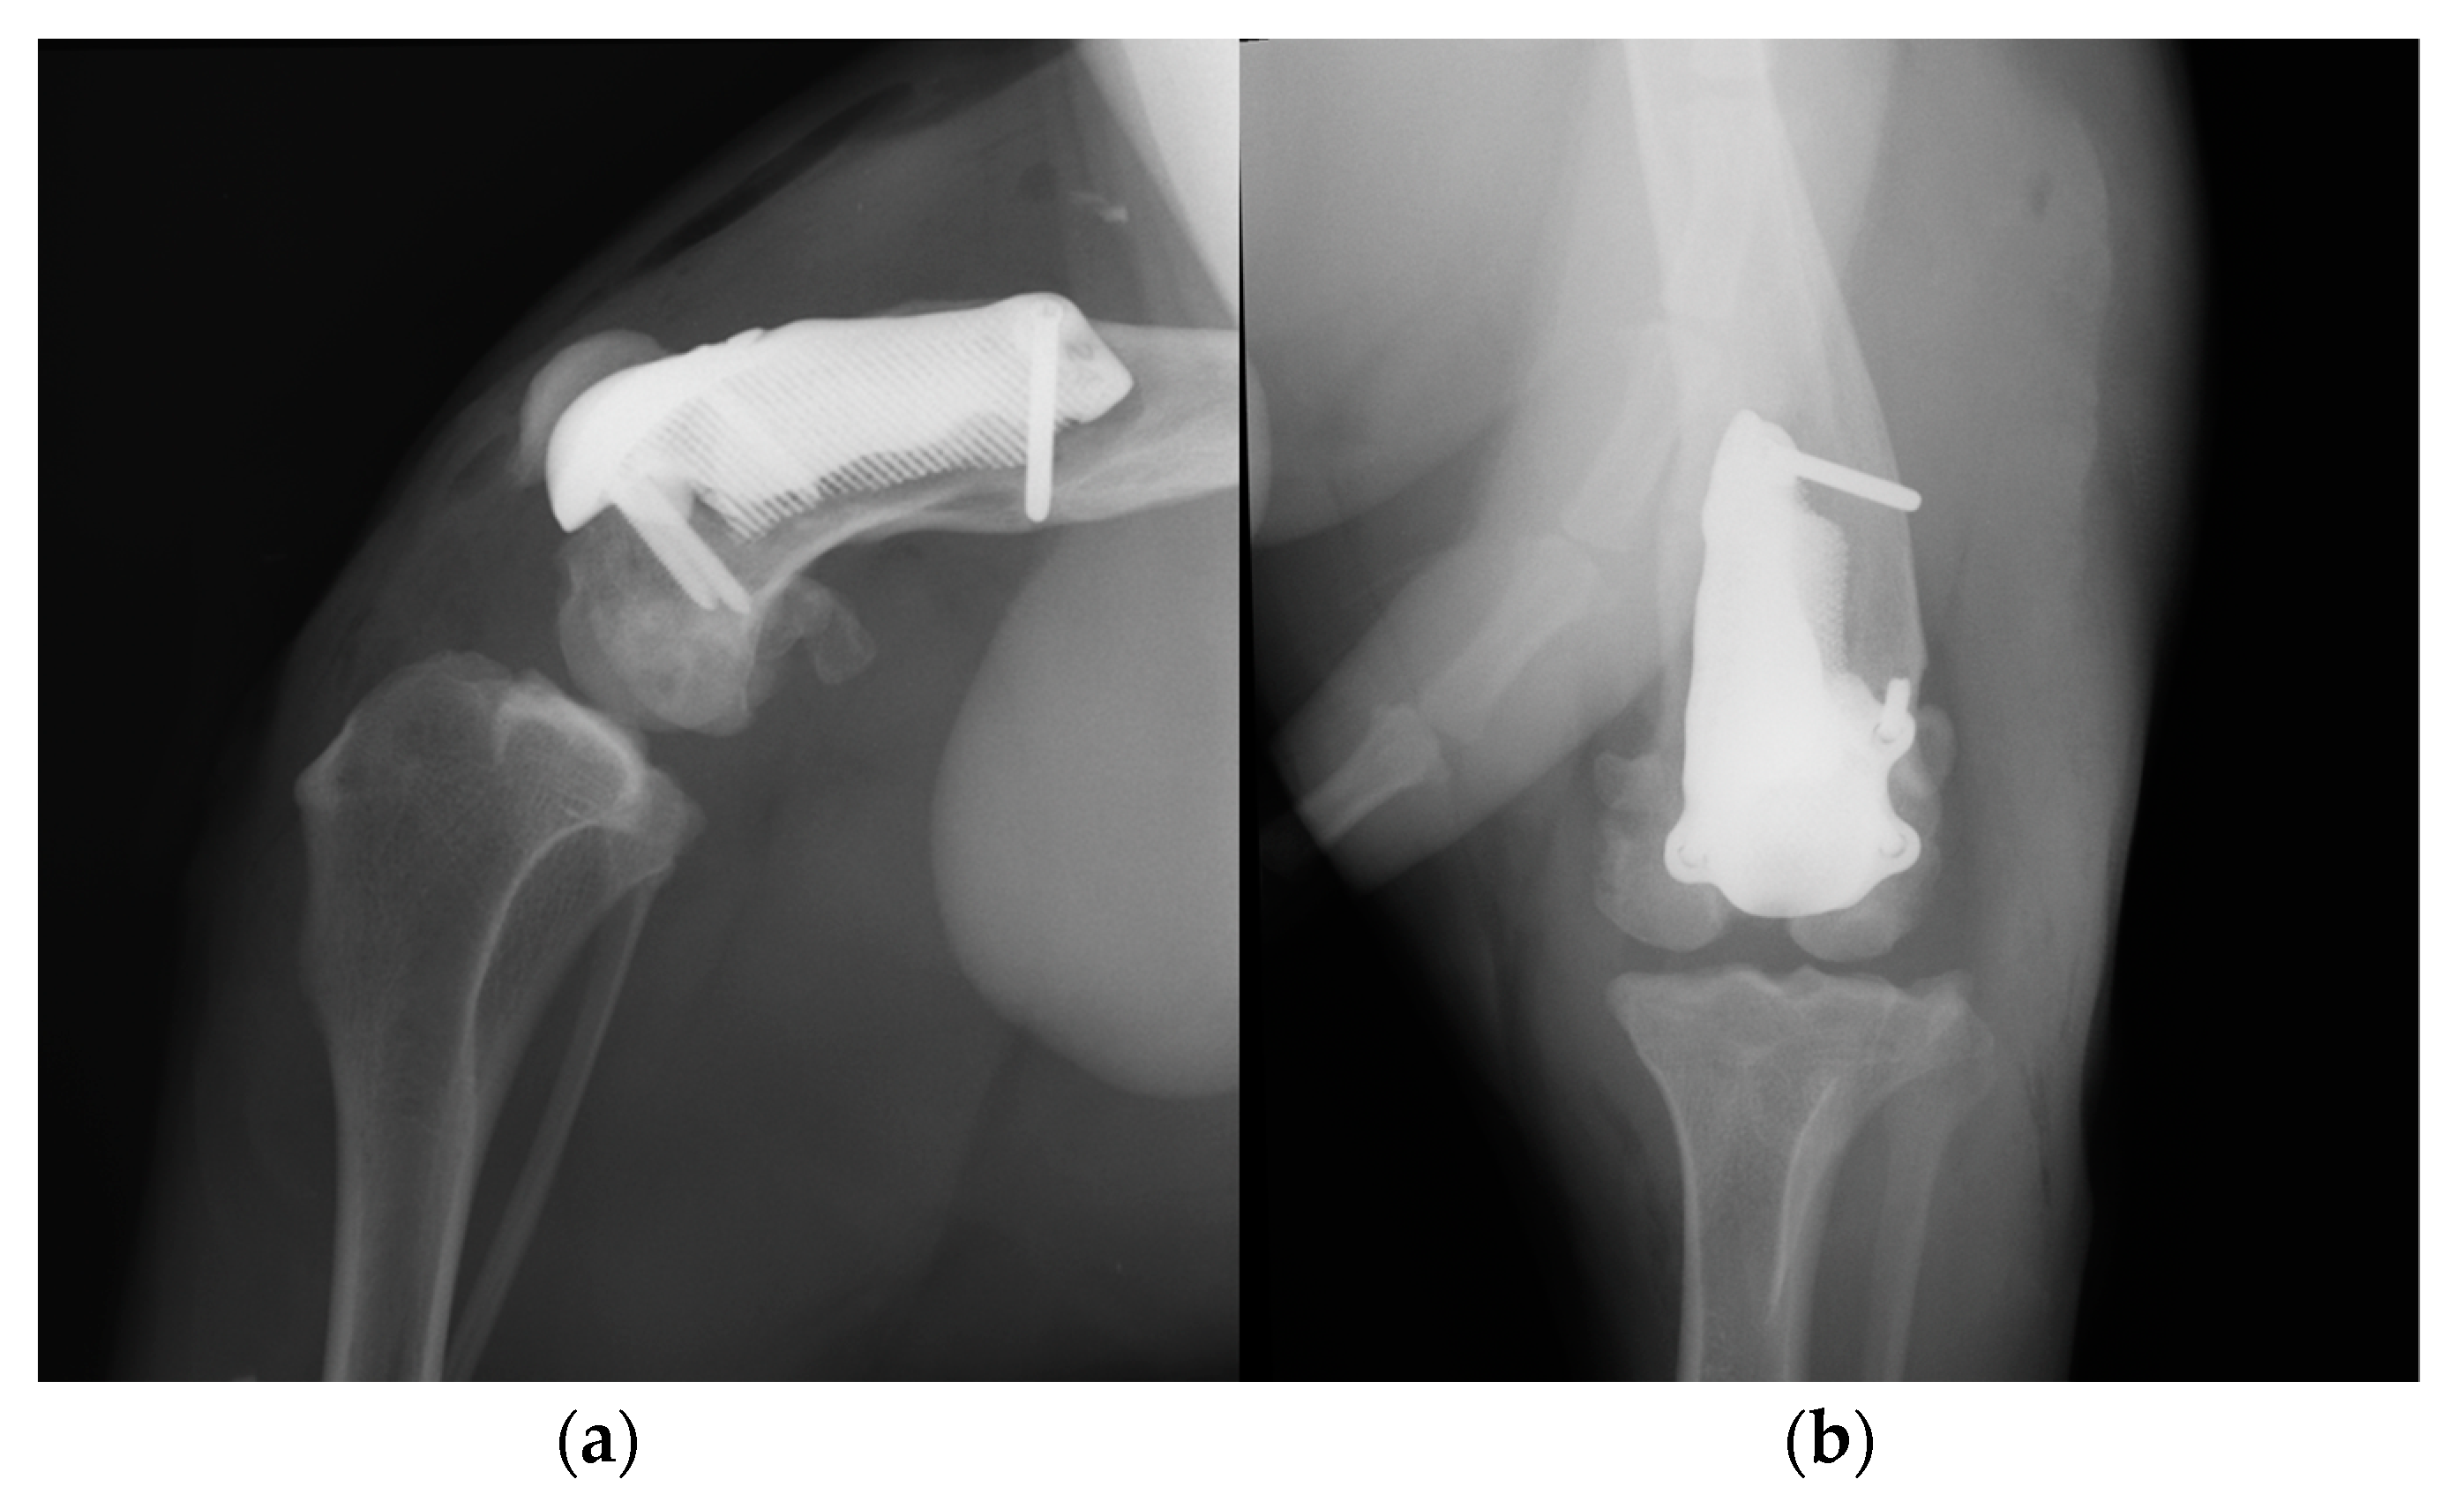

At the 6-, 12- and 18-month follow-up (Video S3c), the orthopedic evaluation revealed crepitus, but a grade 0 right limb lameness and absence of patellar ligament desmitis and palpation of the right stifle joint did not elicit pain. The estimated angle of extension and flexion of the right stifle was 160–80°, respectively, while the ROM of the contralateral healthy limb was 160° in extension and 40° in flexion. The thigh circumference of the pathologic limb was 40 cm compared with 47 cm of the healthy one. The radiographic images showed a good osseointegration of the implant and progression of degenerative changes in the distal pole of the patella (Figure 12).

Figure 12. Twelve-month postoperative medio-lateral (a) and caudo-cranial (b) radiographs of stifle joint showing a good osteointegration of the implant and osteoarthritic changes in the distal pole of the patella compared to postoperative and 3-month postoperative radiographs.